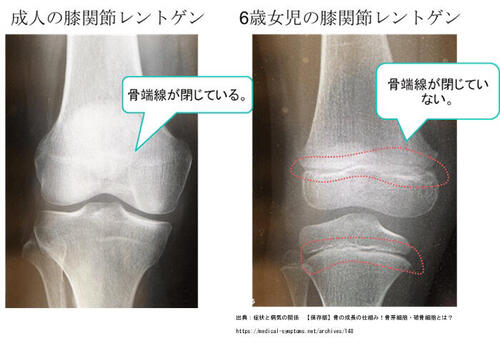

骨端線とはあまり聞覚えがないかもしれませんが、

俗にいう「成長軟骨」というところですね。

成長期のお子さんの骨には「骨端線」という、骨の長さに関係する軟骨層が存在し、

レントゲン撮影をすると骨の端っこに隙間の様に見えます。

この骨端線は成長が止まると隙間が埋まり一本の骨になります。

骨端線は軟骨で形成され強度が弱く、今回のように足首を捻った時や、

手を突き指した時、転んで手を突き手首を捻った際に、

骨端線が離れてしまうケースがあり、これを骨端線離開と言います。